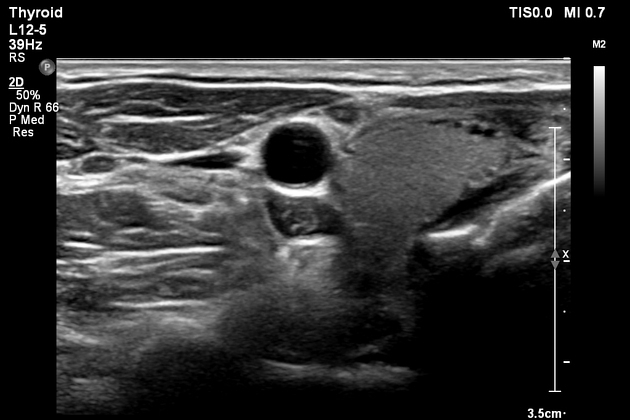

Հանգույցները, որոնք չեն ուղեկցվում գեղձի ֆունկցիոնալ խանգարումներով և չեն ճնշում հարակից կառույցները, ախտանիշներ չեն առաջացնում: Հանգույցի հայտնաբերման դեպքում ախտորոշում կազմելու համար կարող են պահանջվել արյան քննություն, ուլտրաձայնային հետազոտություն և բարակ ասեղային ասպիրացիոն բիոպսիա: